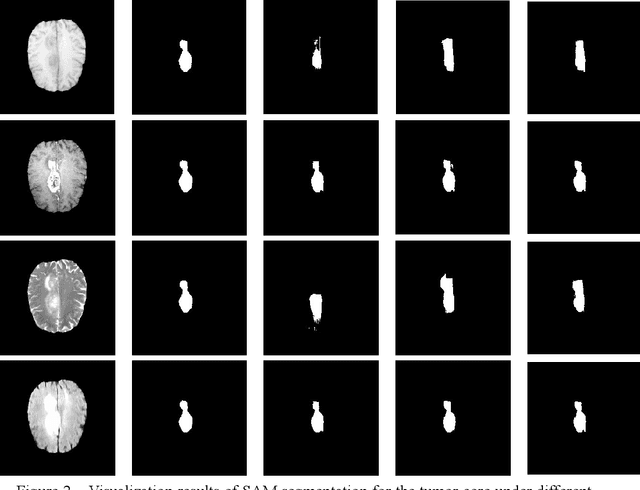

Abstract:Glioma is a prevalent brain tumor that poses a significant health risk to individuals. Accurate segmentation of brain tumor is essential for clinical diagnosis and treatment. The Segment Anything Model(SAM), released by Meta AI, is a fundamental model in image segmentation and has excellent zero-sample generalization capabilities. Thus, it is interesting to apply SAM to the task of brain tumor segmentation. In this study, we evaluated the performance of SAM on brain tumor segmentation and found that without any model fine-tuning, there is still a gap between SAM and the current state-of-the-art(SOTA) model.